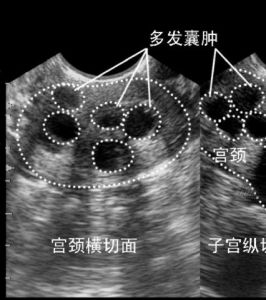

由於慢性炎症的長期刺激,宮頸組織反覆發生充血、水腫,炎性細胞浸潤及結締組織增生,致使子宮頸肥大(cervical-hypertrophy),嚴重者可較正常子宮頸增大1倍以上。炎症痊癒後,充血、水腫減輕或消退,而由於纖維化,宮頸雖已全部被覆鱗狀上皮,表面光滑,但仍維持其已肥大的體積;宮頸腺囊腫亦仍保持其突出的囊狀外形。當腺管被周圍組織所擠壓,腺口阻塞,使腺體內的分泌物不能外流而瀦留於內,致腺腔擴張,形成大小不等的囊形腫物,稱為“子宮頸腺瀦留囊腫”(retentioncystsofthecervicalglands),又稱納博特囊腫(Nabothiancyst)。其包含的粘液常清澈透明,但可能由於合併感染而呈混濁膿性。囊腫一般小而分散,可突出於子宮頸表面。小的僅有小米粒大,大的可達玉米粒大,呈青白色,可能伴有糜爛,但亦常見於表面光滑的子宮頸。宮頸表面有大小不等的清白色囊泡突起,小的如米粒,大的直徑可以超過1厘米。囊腫可以單發,也可以多發,表面光滑。宮頸腺囊腫一般不需要治療,患者也沒有不適的症狀。日常用pH4弱酸性女性護理液清洗外陰保持陰道自潔功能就可。如果囊腫腺體過大,可消毒後用針挑破,有黃白色液體流出!

檢查時可以看到宮頸表面突出多個大小不一的青白色囊泡(並非紫色),內含黏液,小的有米粒大,大的有玉米粒大,有的可以長得很大,突出於宮頸表面,甚至到達陰道口,根部與宮頸之間有蒂相連,常合併有宮頸肥大。

3.B超檢查:B超檢查是診斷女性宮頸囊腫十分常見的一種方式,很多女性通過B超檢查都發現了宮頸囊腫的情況。